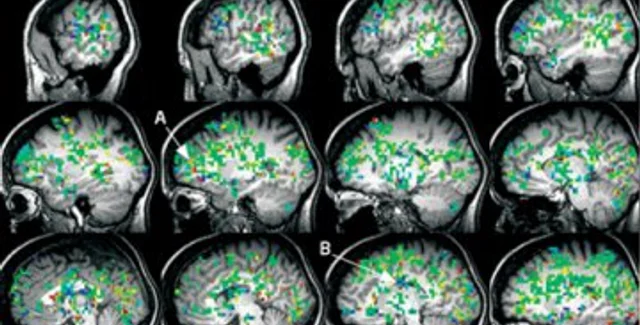

Профессор снял видео с помощью магнитно-резонансной томографии. Это позволило понять, какие области мозга задействованы во время оргазма. Оказалось, активируются более 80 областей человеческого мозга, о чем говорили также показатели кислорода в крови. В том числе и те участки головного мозга, которые отвечают за боль, осязание и память. Кроме того, заметно активизируется предлобная кора. Данный отдел мозга отвечает за воображение.

Во время оргазма почти весь мозг "окрашивался" в желтый цвет. Значит, большинство систем мозга активизировалось. Активность начиналась с сенсорной коры, связанной с гениталиями, но быстро распространялась на лимбическую систему, связанную с эмоциями и памятью.

Момент самого оргазма отмечался пик активности в гипоталамусе, высвобождающем гормон окситоцин ("гормон объятий"). Эксперт надеется, что данное открытие поможет в лечении женщин с сексуальными нарушениями.